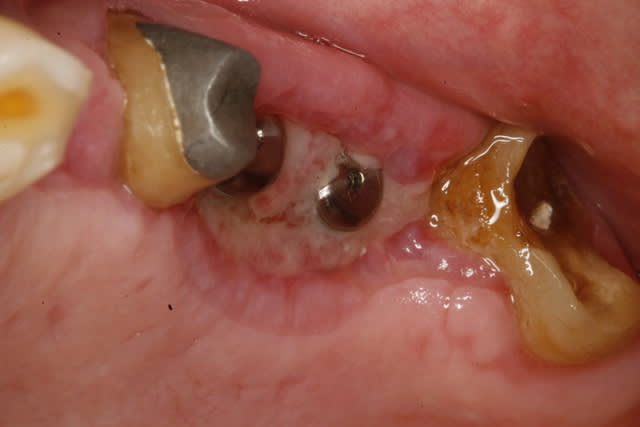

choses promises choses dues voici les photos du cas à J PLUS 18

mg 1013 tputpb - Eugenol